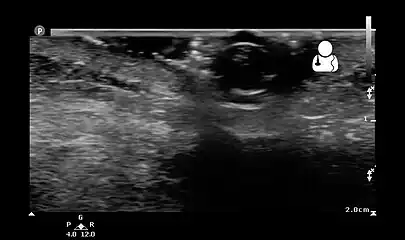

- Ultrasound showing maggot infestation[24]

Ultrasound showing maggot infestation[24]